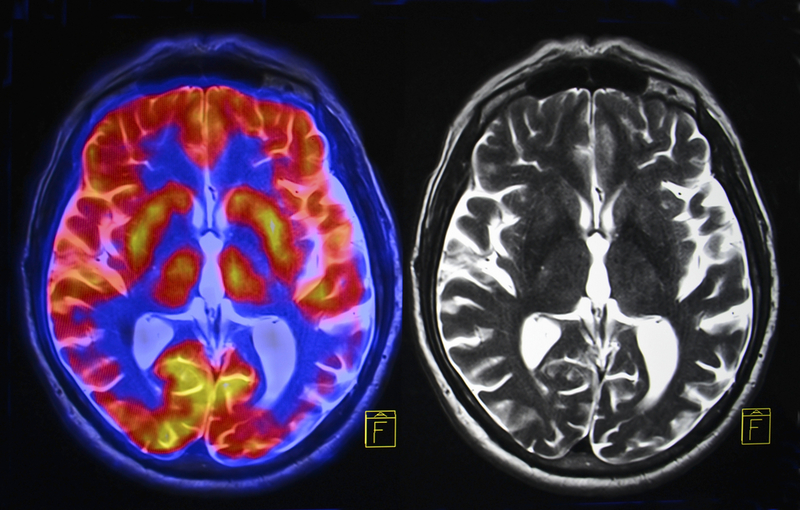

Chinese researchers have built an artificial intelligence (AI) model with medical imaging that would help determine whether patients with severe brain damage might regain consciousness.

Severe brain injury can lead to disorders of consciousness (DOC). Some patients can recover from an acute brain injury but others fall into chronic DOC, also known as a vegetative state. They cannot communicate or act consciously. The novel AI model can make an assessment based on images of brain functional networks, Xinhua news agency reported.

"When a brain functions, multiple brain regions are involved, and they form a network, working together. Like two mobile phones, though no actual wire links them, they have a functional connection when people make a phone call," said lead researcher Song Ming, from the Chinese Academy of Sciences. For the study, published in the journal eLife, the team used resting state functional MRI (fMRI) and found typical features seen in the brain functional networks of DOC patients, which can be biomarkers to trace the level of consciousness and predict the possibility of recovery.

To train the AI, they fed it tens of thousands of brain images of 63 DOC patients, at least one month after their brain injury. The model diagnosed patients who would recover consciousness and those who would not with an accuracy of 88 per cent in 100 cases.